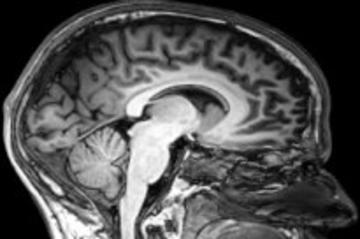

Cross section of a brain in a skull

The Terri Schiavo case illustrates the heated controversy surrounding brain-damaged patients with disorders of consciousness. Some patients have suffered such severe brain damage that they have completely lost the capacity to be aware of themselves or their environment. This is known as the vegetative state. But patients with what is now known as the ‘minimally conscious state’ still possess at least rudimentary and intermittent awareness. These conditions raise difficult ethical questions. Is it in the interest of the patient to continue living in these conditions? Is it ever permissible to let such patients die rather than keep them alive at great cost? Or is life always sacred, and must never be ended, even if living is no longer a benefit to the patient? Can we be confident that awareness is really missing, and can we use neuroimaging to identify consciousness, or even communicate with seemingly non-conscious patients? If consciousness is present, but only in a rudimentary way, would this be a good thing, or rather make things worse, because only conscious patients can suffer?